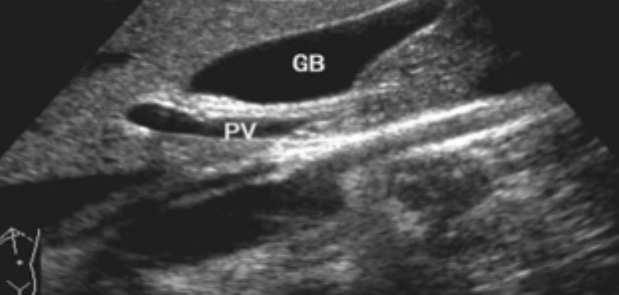

一、正常膽囊超聲圖像有的時(shí)候經(jīng)常發(fā)現(xiàn)檢查不到膽囊,其實(shí)有幾種可能性,檢查人員的技術(shù)不過關(guān)沒發(fā)現(xiàn)膽囊,就要找上級(jí)醫(yī)生會(huì)診,如果還是沒找到的話就不是技術(shù)問題。結(jié)石或腫瘤充滿膽囊,使其液腔消失,慢性膽囊炎使得膽囊萎縮或膽囊壁肥厚而囊腔消失患者已進(jìn)食,膽囊處于膽汁排空的狀態(tài),膽囊先天性過小或缺失;膽囊位置極端異常(可能很低或位于左側(cè))膽囊切除術(shù)后(注意詢問病史)。